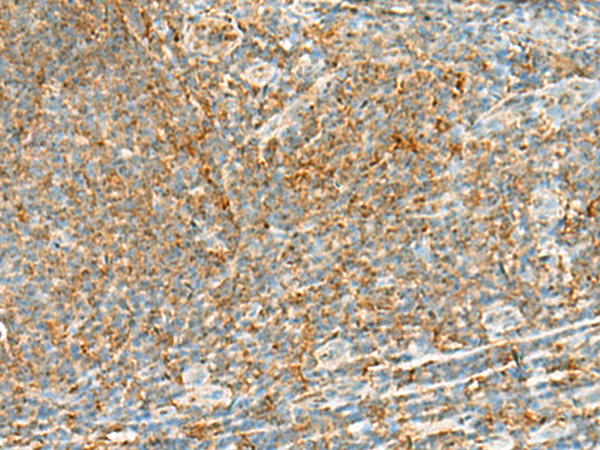

分类: 科研抗体货号: P13561别名: C1orf22应用: IHC反应种属: Human, Mouse